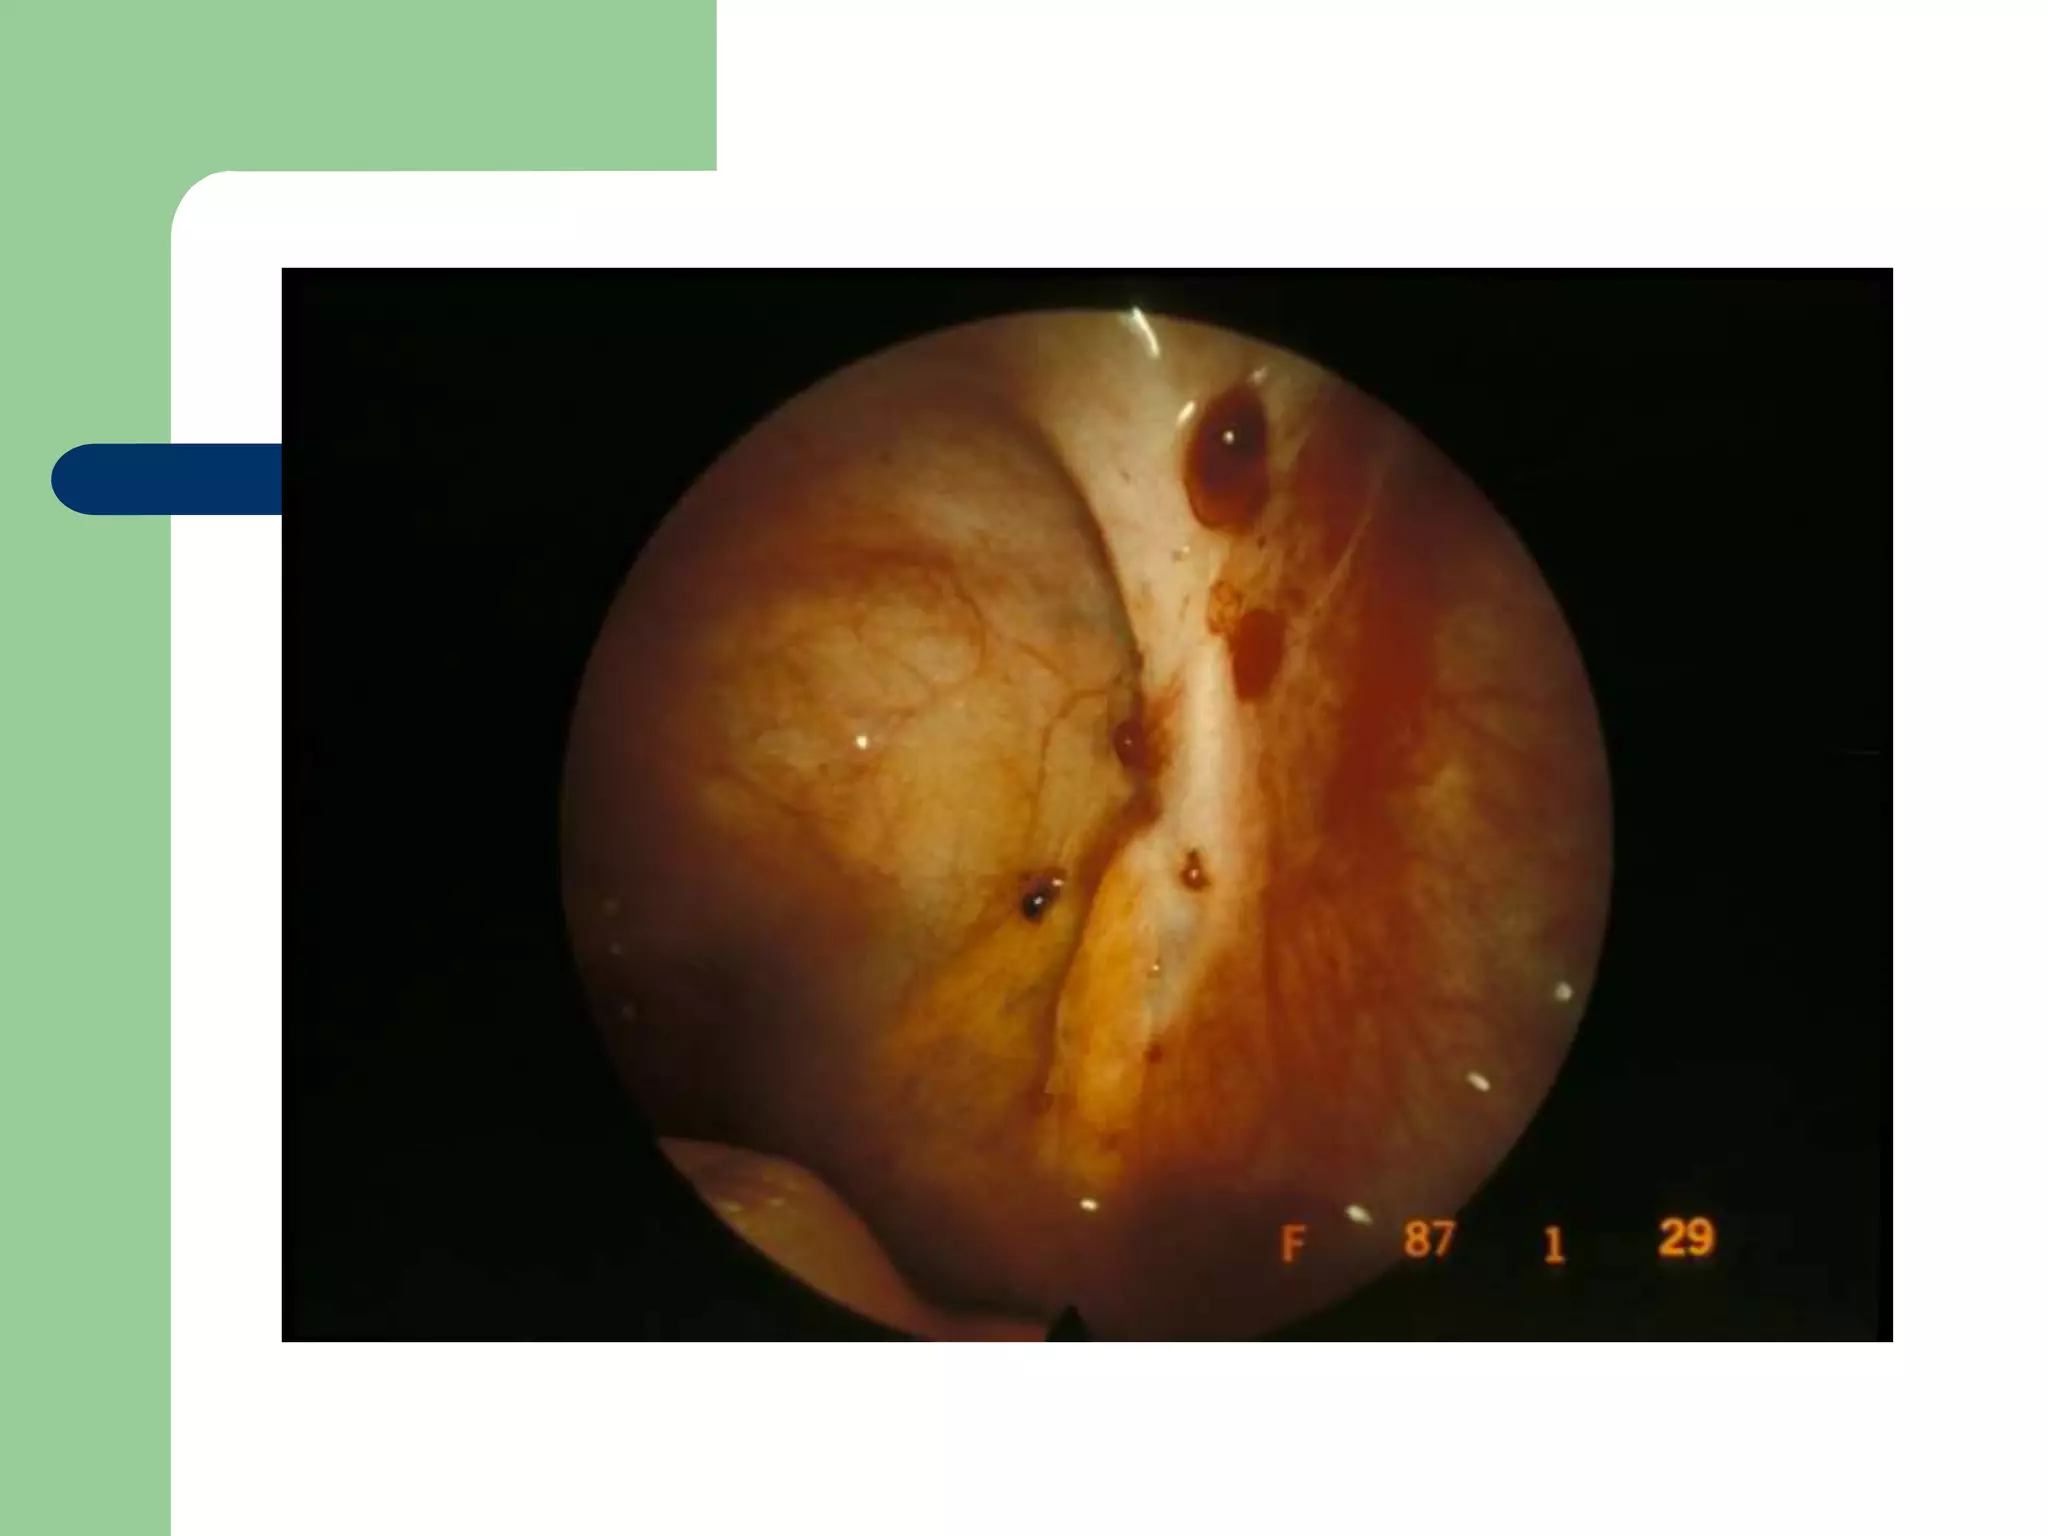

Slide 9

Qs:

1. What is shown in the picture?

2. Name 4 common sites for this lesions.

3. What are the two main ways of treatment?

mention an example for each.

1.Endometriosis (shown by laproscope)

2.Common sites:

Ovaries

Peritoneum

Ovarian/uterine ligaments

Pelvic wall

cervical

3.treatment

1.Medical:

 Pseudopregnency: progesterone pills, OCPs.

 Pseudomenopause: danazole, GnRH

agonists.

2.Surgical:

 Partial or radical either by :Laproscopy or

laprotomy